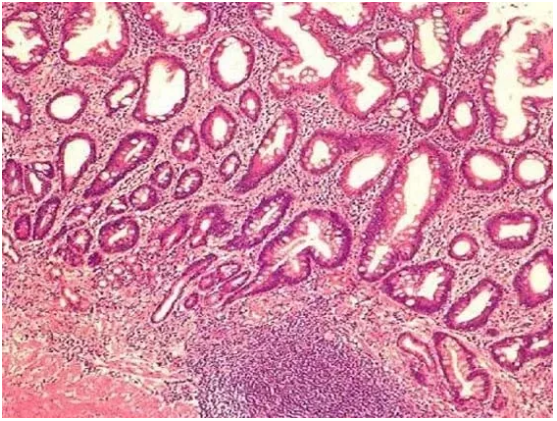

其實,腸上皮化生是一個病理學(xué)名詞,并不是一種疾病,是胃萎縮性胃炎的自我修復(fù)的過程和結(jié)果,指的是胃黏膜上皮細胞被腸型上皮細胞所代替,換句話說,胃黏膜中出現(xiàn)類似小腸或大腸黏膜的上皮細胞。

胃黏膜上皮細胞和腸黏膜上皮細胞主要區(qū)別在于結(jié)構(gòu)不同,顯微鏡下可以通過各自特征性的標(biāo)志來辨別,由于胃黏膜這種結(jié)構(gòu)上的改變看起來和腸黏膜結(jié)構(gòu)很相似,因此病理學(xué)家變將這個現(xiàn)象命名為腸上皮化生。